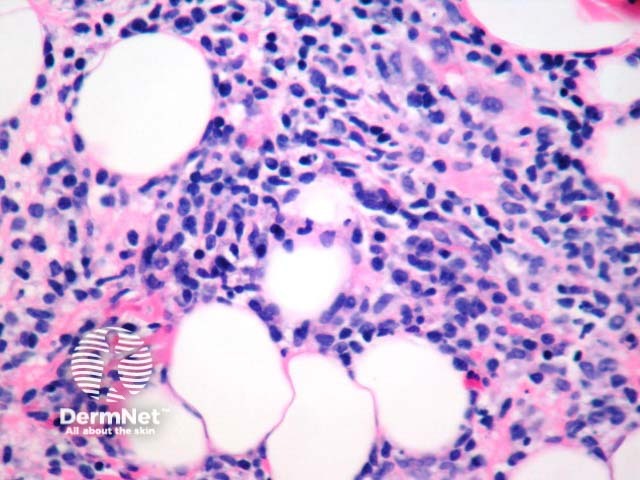

Figure 4 shows the denser infiltrate seen in hydroa vacciniforme-like T cell lymphoma, which may have identical epidermal/superficial changes.

Figure 4

Hydroa vacciniforme-like T cell lymphoma – It is currently unclear whether this is a discrete entity or lies within the spectrum of hydroa vacciniforme. With this lymphoma, the lesions are usually larger, fail to resolve and may also involve non-sun-exposed sites. The infiltrate in the dermis may be denser than seen in hydroa vacciniforme and the subcutaneous fat may be infiltrated (figure 4). Immunohistochemical studies reveal that the infiltrate is composed of CD3+. CD8+, TIA+ T cells or CD56+ NK cells. Gene rearrangement studies may be positive. In-situ hybridisation with EBV may be positive in the infiltrate.